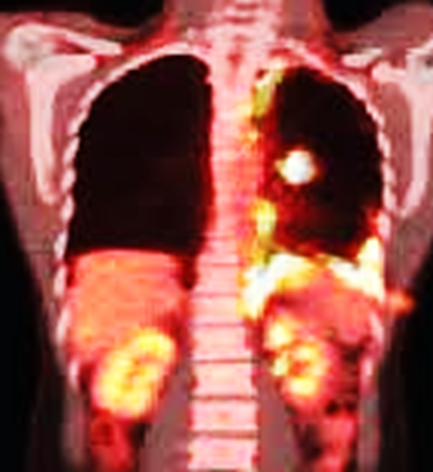

PET-CT:

• Talc can cause increased FDG uptake, mimicking malignancy.

• Uptake may persist for months or years, especially in areas of inflammation.

5. Talc deposits demonstrate FDG avidity on F-18 FDG PET/CT.

Explanation: Intense FDG uptake due to granulomatous inflammatory response can persist for decades.

• CT: Nodular or linear pleural thickening with variable degrees of calcification. The findings are expected to remain stable over serial imaging.

• F-18 FDG PET/CT: FDG avidity may be observed in areas of pleural thickening resulting from talc pleurodesis.